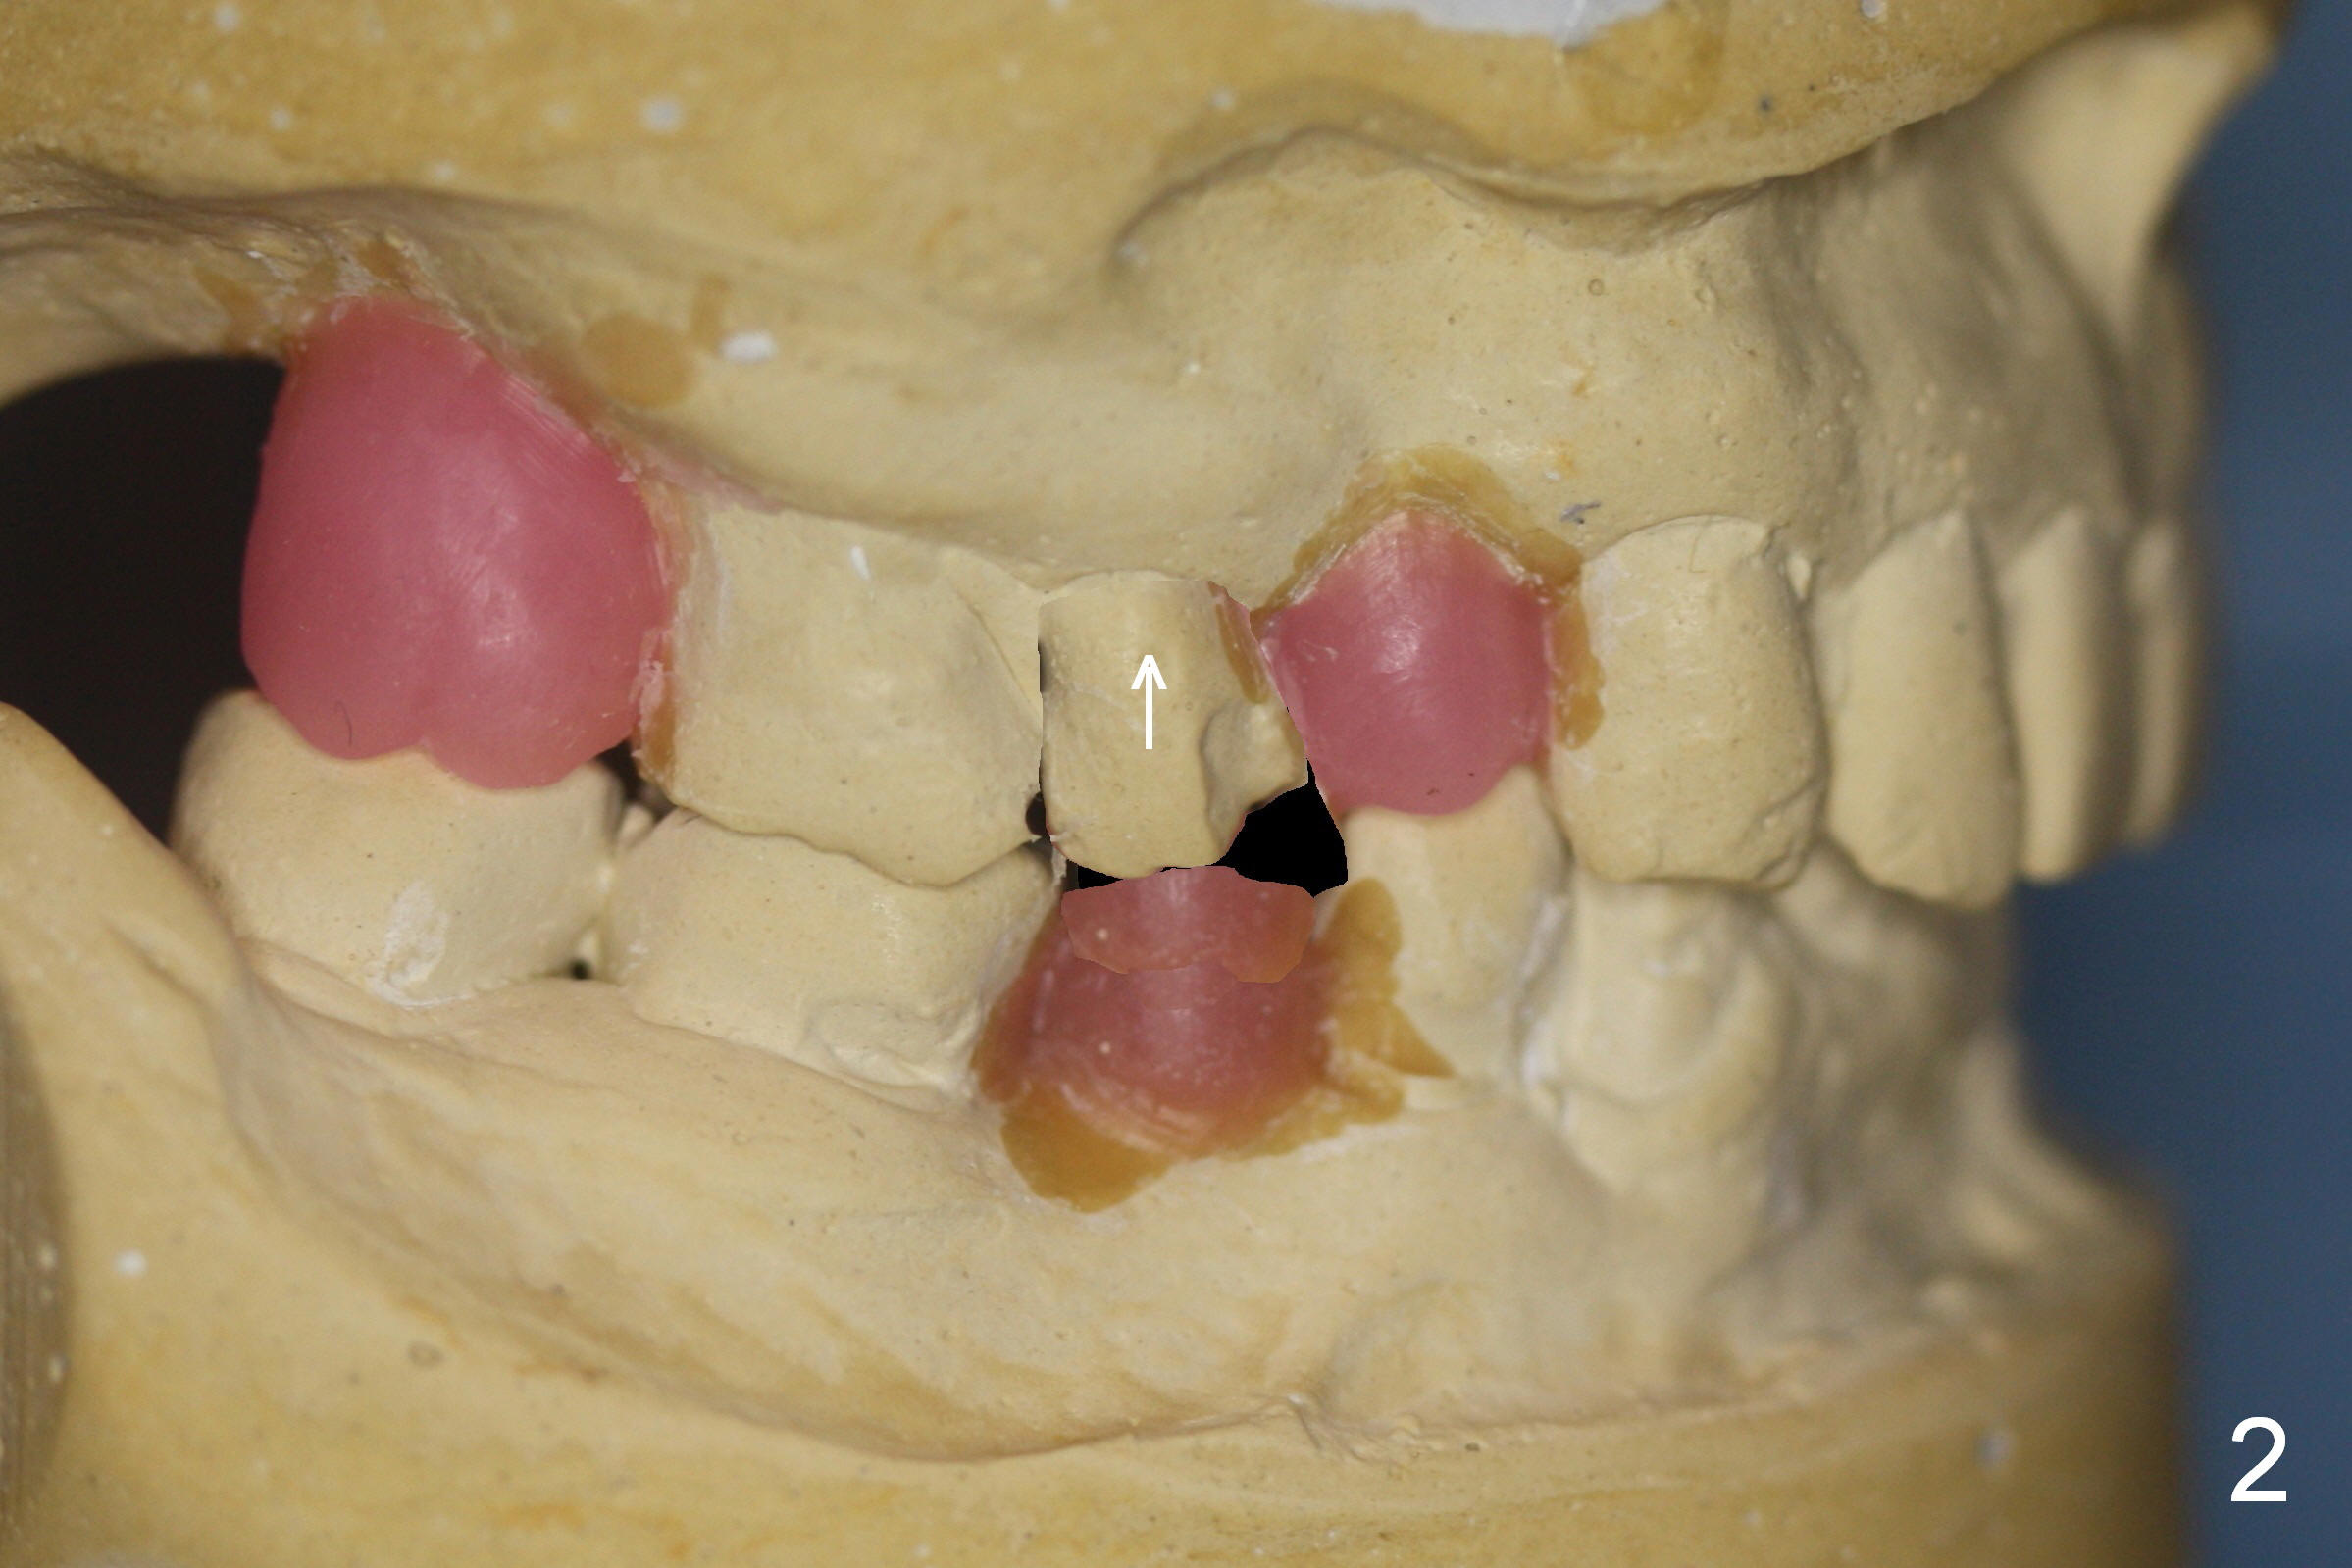

A 56-year-old man has long-termed partial edentulism (#2,5,14,15 (not shown),29, Fig.1). There is supraeruption of the opposing teeth (Fig.1 arrows). If an immediate provisional is provided, it should have plenty of clearance to avoid micromovement of the implant. Once the implants at #2,5, and 29 osteointegrate, they will be used as anchorage for intrusion (Fig.2,3 arrows, segmental orthodontics).